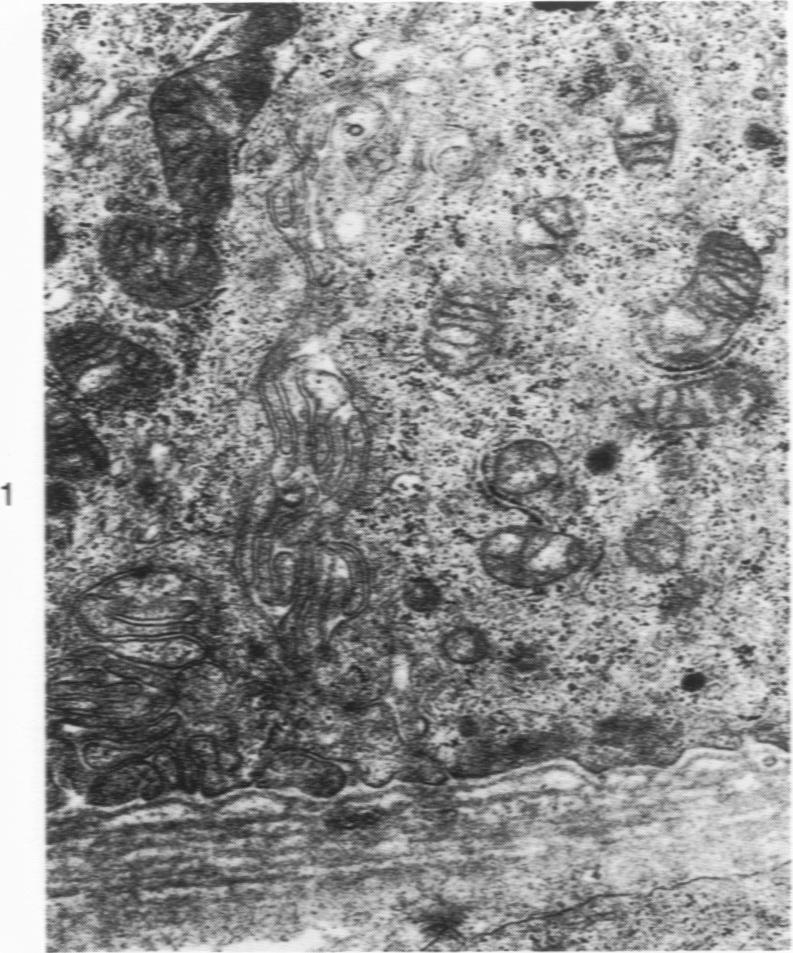

Electron microscopy of nephropathia epidemica. Renal tubular basement membrane.

Tubular basement membranes in kidney biopsies from 18 patients with nephropathia epidemica were studied by electron microscopy. Both in the cortex and in the medulla there was splitting of the basement membrane. Thickened basement membrane around occasional tubules contained membrane vesicles, usually empty but also with a core and a diameter of approximately 180 nm. Membranous convoluted structures and light finely fibrillar areas in the basement membranes were seen. Splitting of the basement membrane was most prominent in the medulla, and the membrane was filled with round to oval particles 55 to 470 nm in diameter. Of the possible mechanisms of damage at the basement membrane level in this disease, the findings suggest liberation of antigen from the tubular cells and reaction of circulating antibodies with the antigen in the basement membrane.